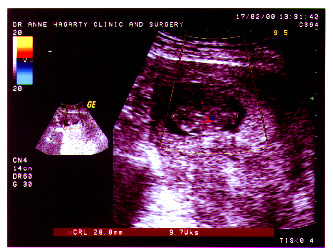

| Yep, there's another one on the way. We're still really early on in the game, with the finish line way off on September 18th.

This was taken at 9 weeks. |